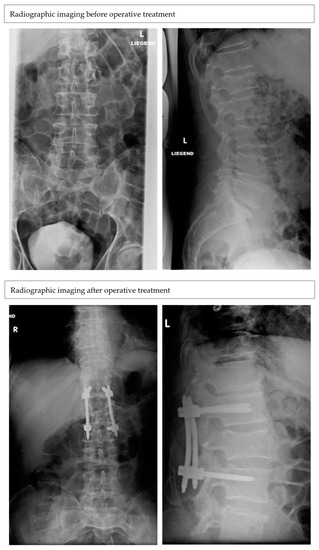

Radiographic Outcomes of Conservative and Operative Treatment in Isolated L1 Fractures

3. Results